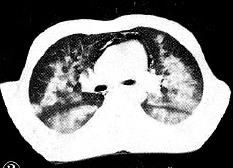

下图是非常典型的蝶翼征。

再来一个更直白的蝶翼征,几乎可以翩翩起舞了。